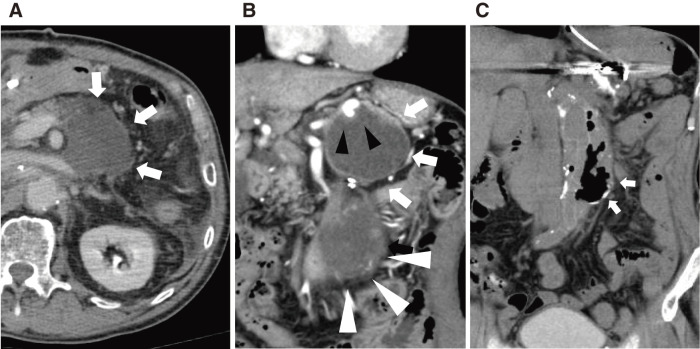

一名 60 多岁的男子因腹主动脉瘤破裂接受了开腹移植物置换术,术后出现了胰腺假性囊肿。患者接受了内窥镜引流术,但由于移植物周围空腔大面积沟通,导致主动脉移植物感染。为了同时处理胰瘘和移植物感染,患者接受了经皮引流术。虽然胰腺假性囊肿缩小了,但主动脉移植物感染仍然存在。随后,进行了主动脉移植物部分置换术,并用大网膜瓣覆盖。他口服抗生素后出院,10 个月后感染没有复发。

A man in his 60s developed a pancreatic pseudocyst postoperatively after an open graft replacement for a ruptured abdominal aortic aneurysm. Endoscopic drainage was performed; however, this led to an aortic graft infection due to macroscopic communication with the perigraft cavity. Percutaneous drainage was performed to manage the pancreatic fistula and graft infection simultaneously. Although the pancreatic pseudocyst diminished, the aortic graft infection persisted. Subsequently, partial aortic graft replacement with greater omental flap coverage was performed. He was discharged with oral antibiotics, with no recurrence of infections at 10 months.